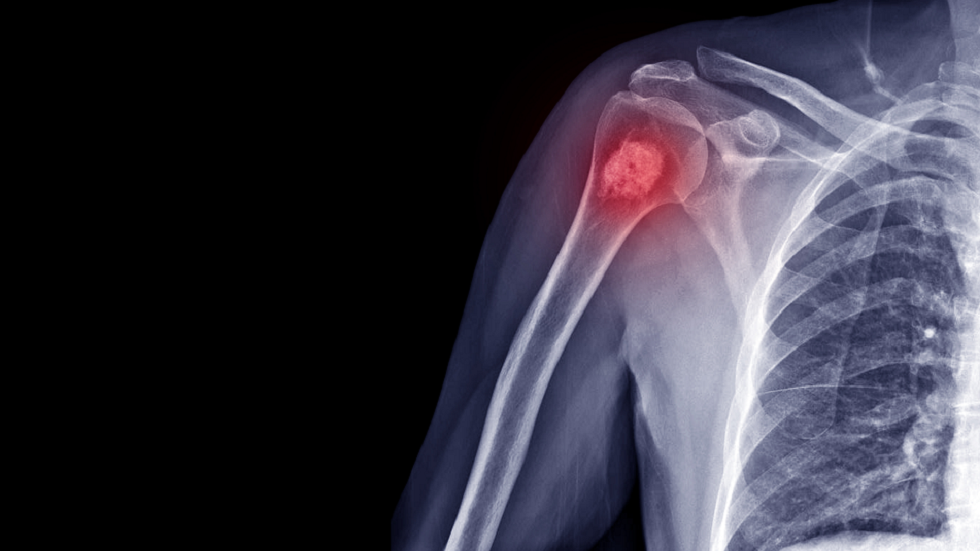

يعد سرطان العظام من أندر أنواع السرطان، ويكون أكثر شيوعًا في العظام المشتركة مثل الفخذ والساق والأذرع.

أعراض سرطان العظام

ألم في المنطقة المصابة، وقد يكون هذا الألم مستمرًا أو يزداد تدريجيًا.

تورم في المنطقة المصابة.

ضعف عام في الجسم وفقدان الوزن غير المبرر.

الكسور العظمية الغير مبررة أو السهولة في حدوث الكسور.

التنميل أو الشعور بالخدر في المناطق المجاورة للورم.